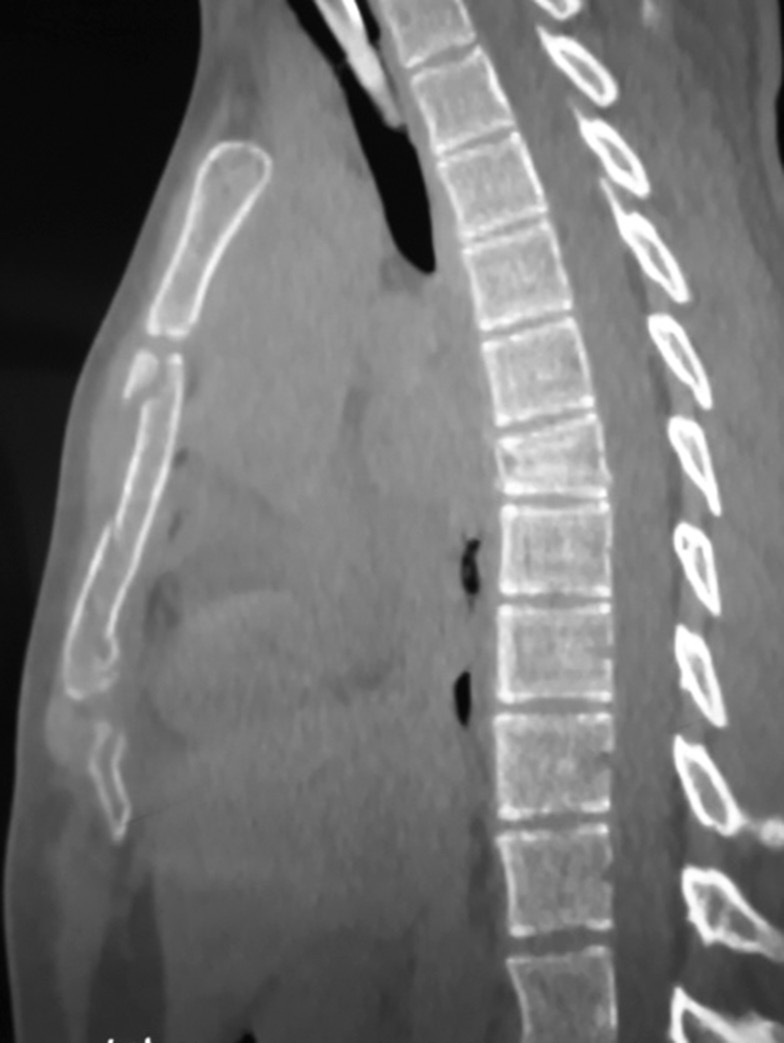

Проведение КТ позволило во всех случаях достоверно подтвердить переломы позвонков и определить характер повреждений грудины (рисунок).

Рисунок. Компьютерная томограмма грудного отдела позвоночника и грудины пациентки В., 16 лет. Компрессионный перелом тела позвонка ThVII. Оскольчатый перелом грудины (тип по классификации АО/АТО: 16.3.2.С)